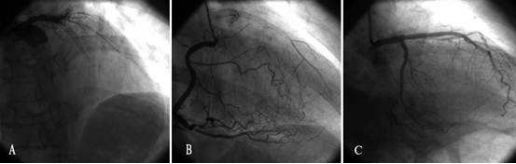

冠脈造影,即心臟造影手術(shù),是診斷

冠心病常用且有效的方法,被視為不受威脅可靠的診斷技能,是診斷冠心病的“金標(biāo)準(zhǔn)”,目前已經(jīng)廣泛應(yīng)用于臨床中,日本在這一手術(shù)上做的比較好。

日本心臟造影手術(shù)不僅可以確定冠狀動(dòng)脈是否存在阻塞以及阻塞的嚴(yán)重程度,還可以為下一步的治療方案提供依據(jù)。

其實(shí),這樣的想法是多余的。專家解釋道:“冠脈造影就是用一根細(xì)細(xì)的造影心導(dǎo)管,經(jīng)大腿的股動(dòng)脈或前臂的橈動(dòng)脈將導(dǎo)管送到冠狀動(dòng)脈的開口處,通過導(dǎo)管向冠狀動(dòng)脈注入造影劑,直接觀察冠狀動(dòng)脈病變的位置、狹窄程度、病變性質(zhì)。

它不僅可以了解到心臟功能和血管之間有無側(cè)支循環(huán),有無解剖畸形等,還對(duì)判明病變是否需要外科手術(shù)、介入血管成形術(shù)或藥物治療等有重要指導(dǎo)意義。這個(gè)過程大約需要10-15分鐘。手術(shù)結(jié)束后,導(dǎo)管將被抽出,在手腕動(dòng)脈處行人工壓迫治療,防止出血?!?/div>